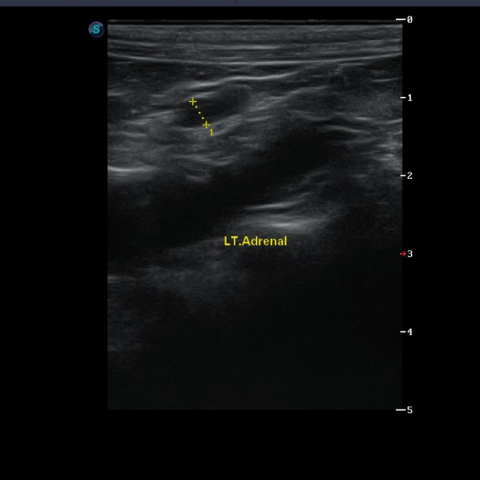

Á¤»ó ÁÂÃø ºÎ½Å